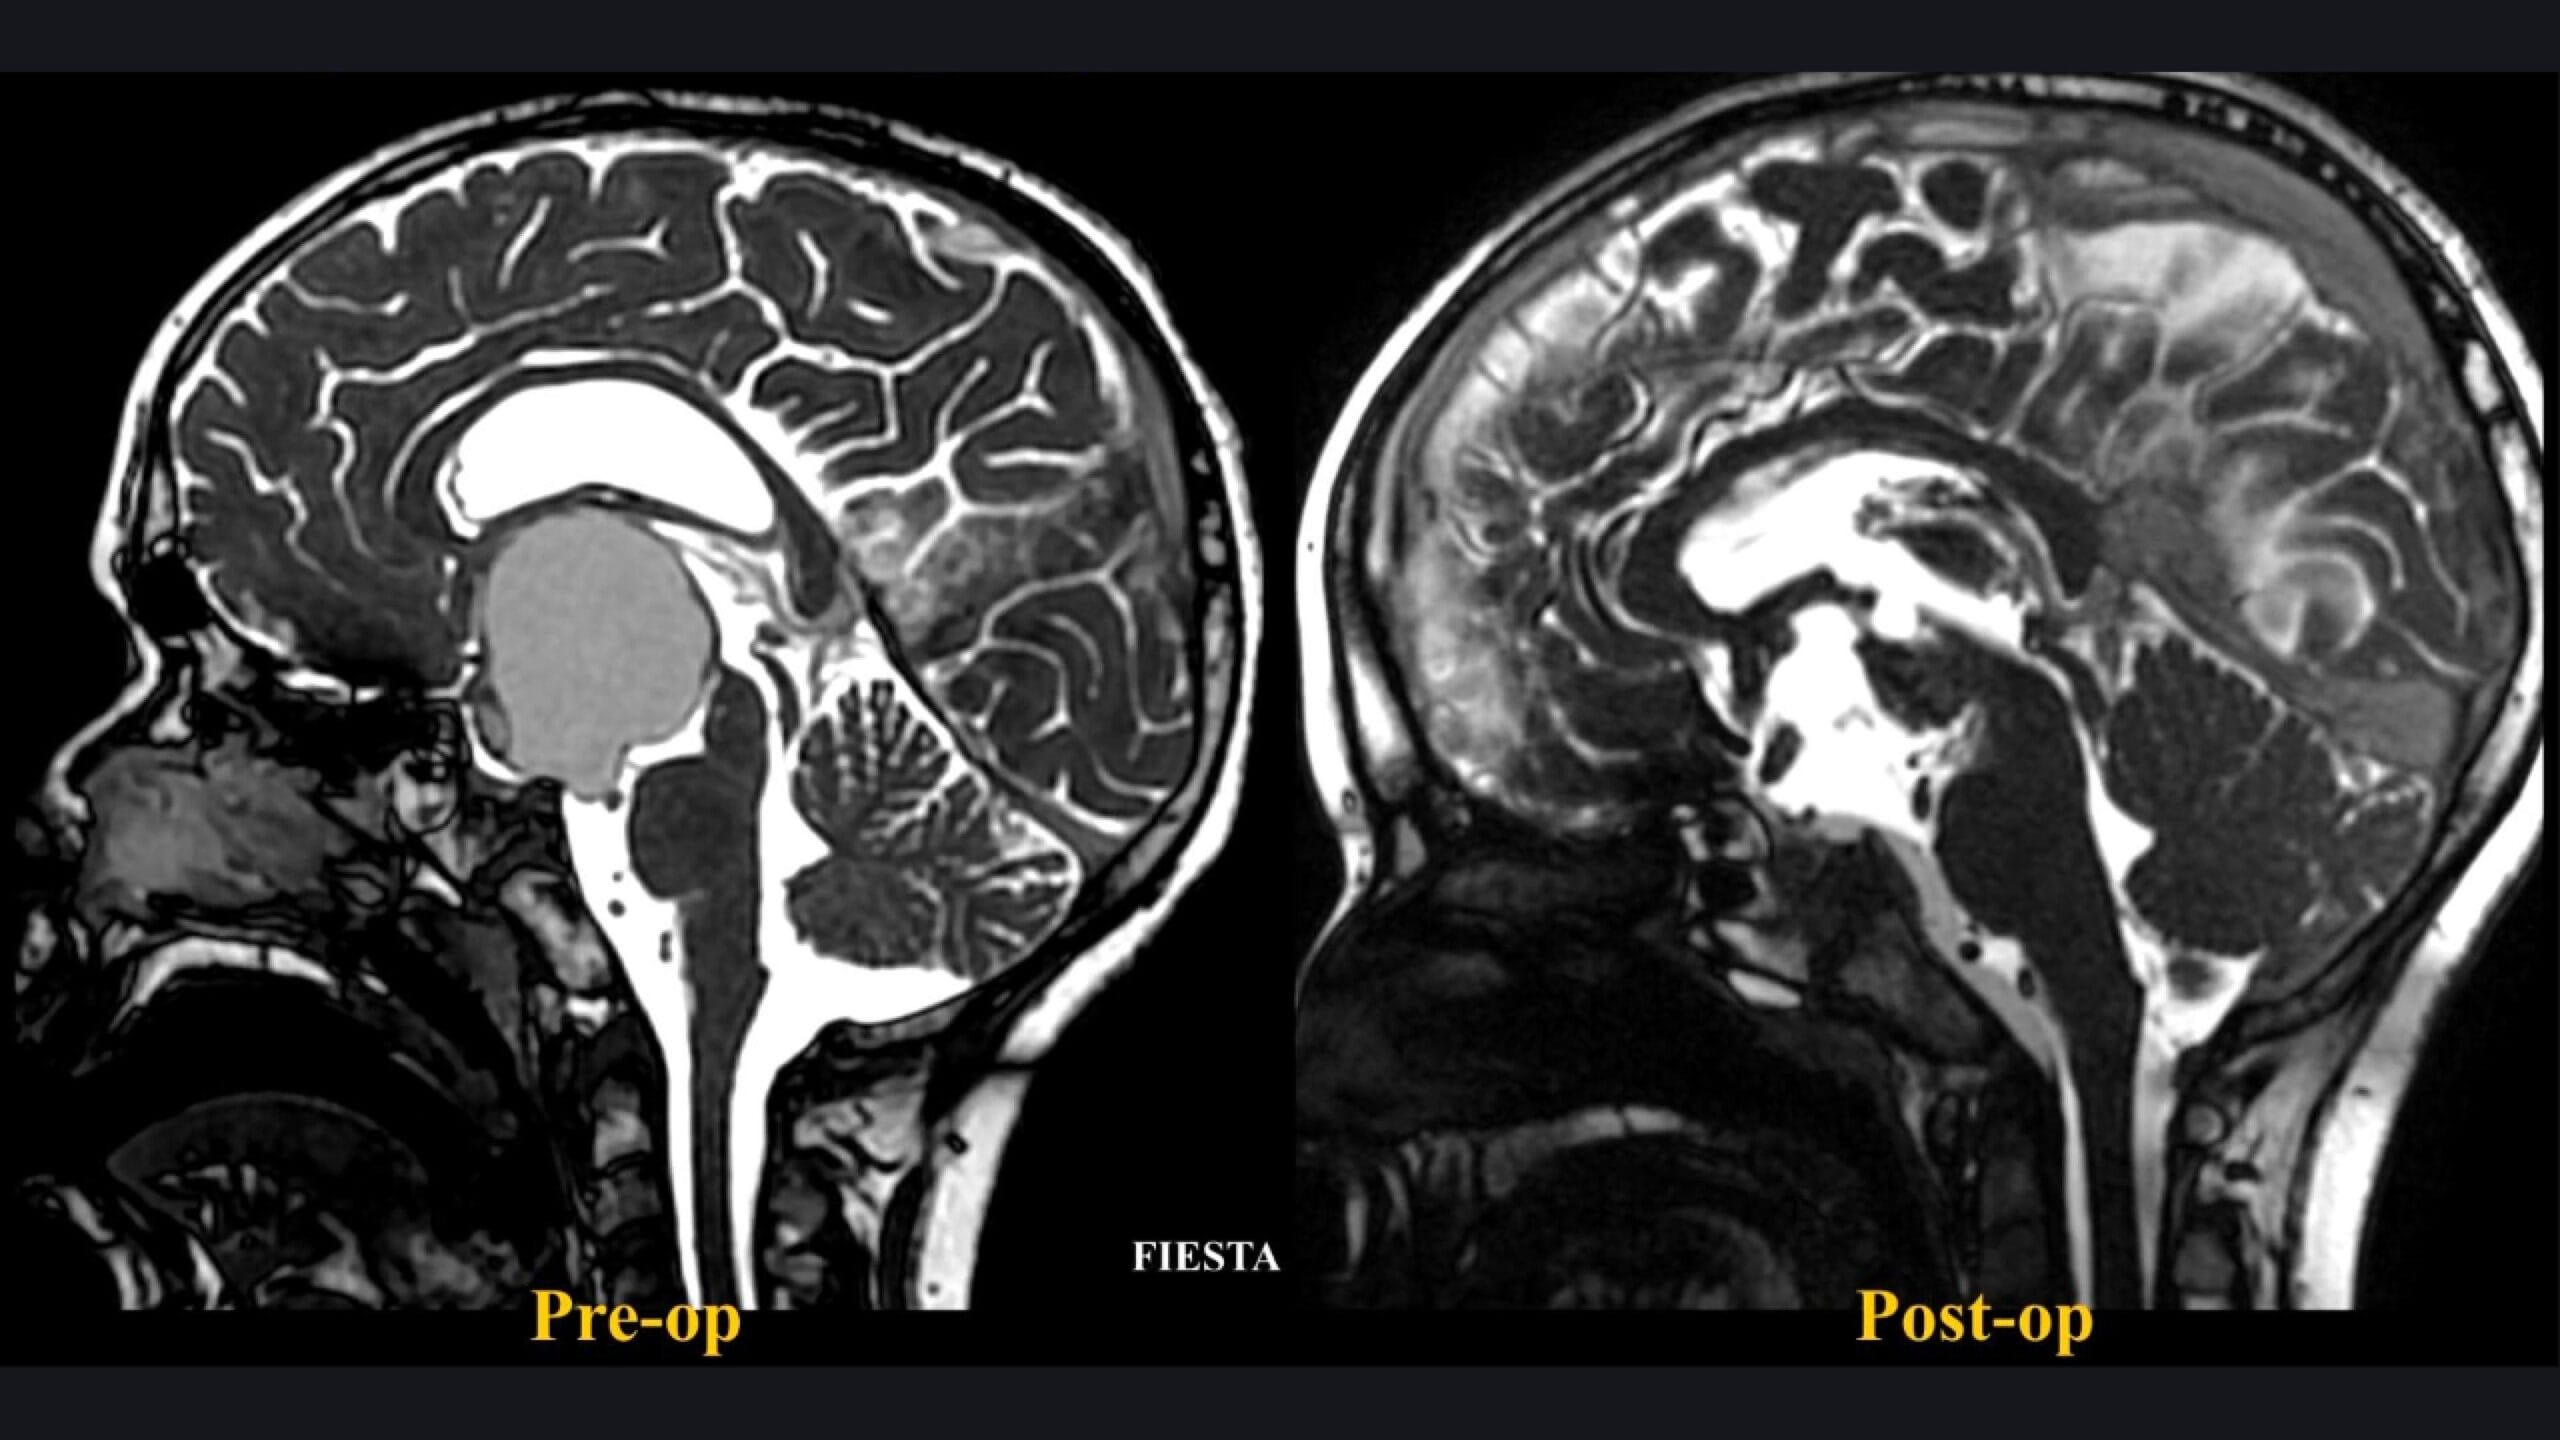

La resonancia magnética evidenció una masa sólido-quística de 4,5 × 3,6 × 3,3 cm, con marcada extensión supraselar, obliteración del tercer ventrículo y proyección hacia las cisternas interpeduncular y prepontina. El nódulo mural reforzaba heterogéneamente, con calcificaciones visibles en la tomografía. El patrón vascular mostraba una arteria cerebral posterior fetal derecha y arterias cerebrales anteriores no desplazadas superiormente, hallazgo clave que confirma un origen retrochiasmático.

- Resección completa en neuroimagen.